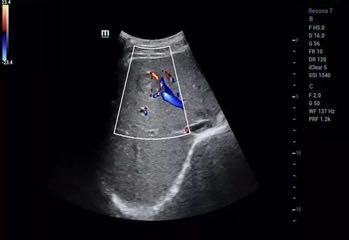

图1 肾脏二维图像及彩色多普勒图像

(彩色多普勒清晰显示肾脏血管分布及血流情况)